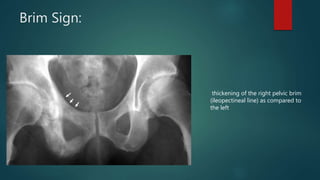

Brim Sign:

thickening of the right pelvic brim

(ileopectineal line) as compared to

the left

Brim Sign: thickening ofthe right pelvic brim (ileopectineal line) as compared to the left